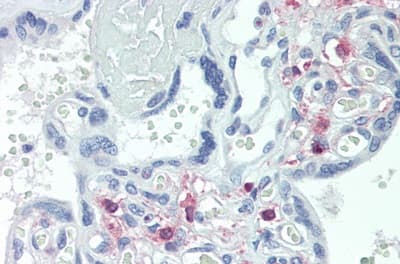

Rabbit Polyclonal TRPC6 antibody. Suitable for WB, IHC-P and reacts with Pig, Human samples. Cited in 1 publication. Immunogen corresponding to Recombinant Fragment Protein within Human Short transient receptor potential channel 6 aa 1-200.

Applications IHC-P, WB

Species Reactivity Human, Pig